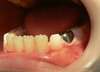

Elle trouve son indication dans les cas de délabrements ou d’anomalies de structure de la dent temporaire. La couronne pédiatrique préformée permet non seulement de restaurer anatomiquement la dent le plus fidèlement possible, mais également de maintenir l’espace dans le sens de la longueur et de la hauteur.

En rétablissant l’harmonie, elle permet à la dent permanente sous-jacente d’évoluer normalement sur l’arcade.